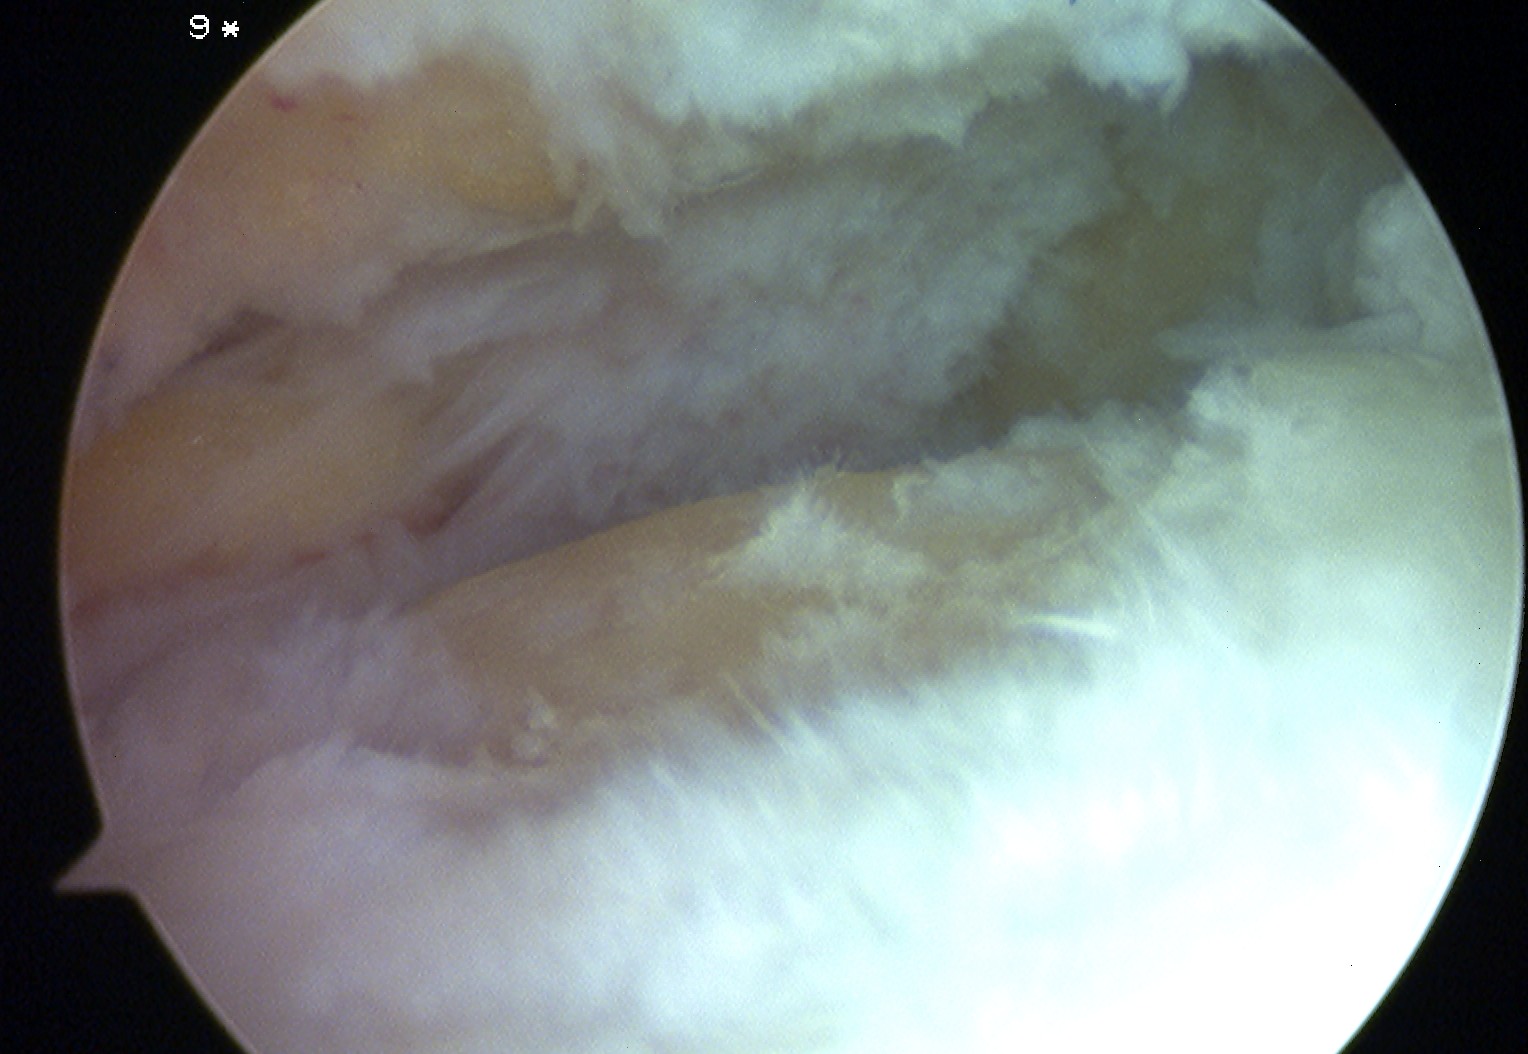

• Arthroscopy